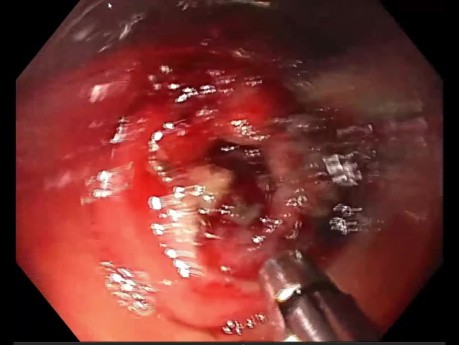

Contrôle des Saignements pendant la Dissection...

Cas vidéo ESD : la pince à coagulation est l'appareil maître, pour toute dissection sous-muqueuse endoscopique ou mucosectomie. Contrôle d'un saignement avec la pince à coagulation Forced Coag 5.0.